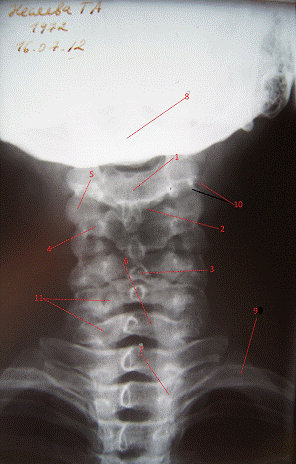

Рентгеновские снимки шейного отдела позвоночника: анатомические особенности